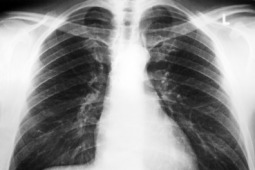

Jak podaje gazeta najczęstszą postacią choroby jest gruźlica płuc. W 2013 roku stanowiła ponad 94 procent wszystkich przypadków. Najwięcej osób ze schorzeniem jest w grupie powyżej 65 lat. W 2012 roku gruźlica była w naszym kraju przyczyną zgonu 630 osób.